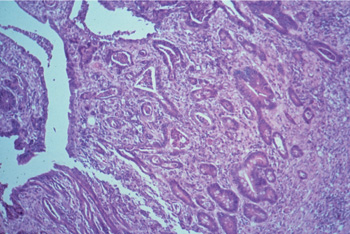

Histopathological findings vary but in all cases the baseline is as follows: In small intestine villi are short or completely lost and the surface epithelium is cuboidal or flattened. Lymphatics may be distended. The mucosa is thickened by proliferating crypts, which is the same in caecum and colon. There are four to five layers of intensely stained epithelial cells and goblet cells are sparse or missing. The mitotic rate in crypts is increased and in some crypt lumina cellular debris is accumulating(see pict 5.2.1 b). In comparison to an uninfected mucosa (see pict. 5.2.1 c), there is a mild to moderate inflammatory response in the lamina propria, sometimes even extending in deeper layers.

Picture 5.2.1 b (by J. Pohlenz)

Porcine ileum with PIA: Short intestinal villi covered with flat to cuboidal epithelial cells, sub epithelial oedema and proliferating crypts. There are two to three layers of crypt epithelial cells, loss of goblet cells, increased numbers of mitotic figures and intraepithelial cells, and a mild to moderate inflammatory reaction in the lamina propria (~125x).